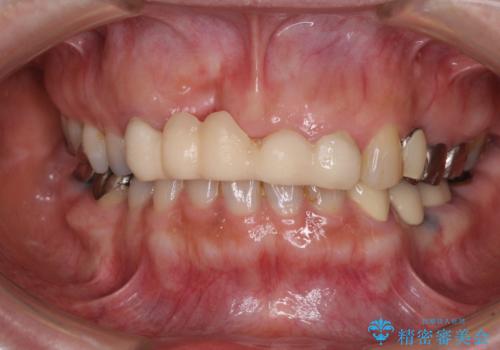

- 前歯のブリッジ治療中に装着していた仮歯が、あまりにも不自然で気になるとのことで来院された患者様です。

早急に仮歯をきれいなものに付け替え、オールセラミックブリッジにより補綴することとしました。

仮歯に置き換えた時点で見た目が大きく改善され、人目を気にすることがなくなりました。

オールセラミッククラウンは、本物の歯のような外観となり、患者様には大変満足していただけました。